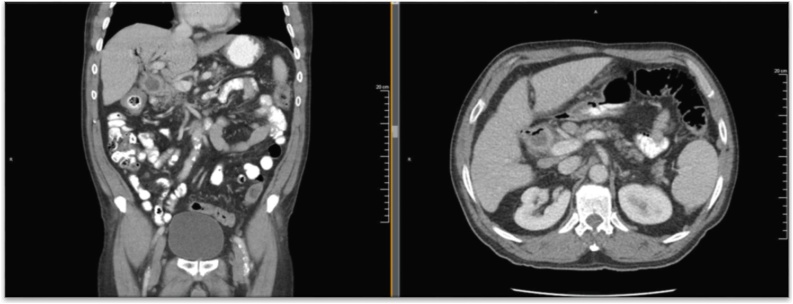

Ultrasound (US) imaging demonstrated a thickened gallbladder wall up to 5 mm with an apparent shadowing suggesting a gallstone as well as some pericholecystic fluid. Due to extensive ring-down artifact on US, computed tomography (CT) imaging was obtained and elicited concern for cholecystocolonic fistula (Fig. 1); with pneumobilia, inflammation and enhancement in the area of the gallbladder fossa and common bile duct (CBD), as well as thickening extending into the adjacent colon at the hepatic flexure. The patient underwent two weeks of antibiotic therapy. Preoperative Hepatobiliary scintigraphy was compatible with a cholecystocolonic fistula to the hepatic flexure of the colon (Fig. 2). However, preoperative colonoscopy was unable to locate the fistula tract.